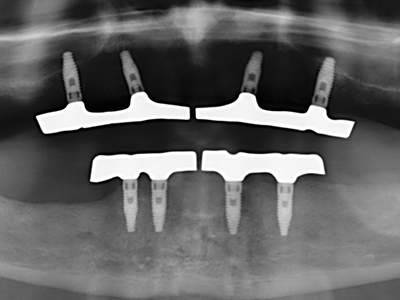

Костната тъкан е не само минерализирана структура, тя съдържа и съществено количество колагенови влакна. Това означава, че тя има не само добра компресивна сила, но и известна степен на гъвкавост, която може да се възприеме като предимство при извършване на костна аугментация. В класическата процедура по разширяване чрез костно разделяне, атрофиралият алвеоларен гребен е разделен надлъжно и внимателно разширен след достигане на подходящата остеотомна дълбочина (Фиг. 13-16), в идеалния случай без допълнително отстраняване на периостеума (Brugnami, Caiazzo et al. 2014, Stricker, Fleiner et al. 2014). Системите с винт и пластини с увеличаване на разстоянието при разширяване са доказали ефективността си при разделяне на двете костни ламели, оставайки под прага на фрактурите. В общи линии, оставащата ширина на костта от поне 3–4 mm е задължителна (Chiapasco, Zaniboni et al. 2006), за да се гарантира добра гъвкавост и достатъчно костно покритие за бъдещото поставяне на импланти. Ако е необходимо, вертикалната остеотомия на едната или двете страни може да подобри гъвкавостта. Комбинацията с допълнителни техники за аугментация, особено в букалната страна, е описана като алтернатива на класическата техника.

Процедурата по разделяне е атравматична и няма голяма загуба на пространство, използвайки пиезотриони, и няма значителна разлика между импланти в разделени челюсти и импланти в алвеоларния гребен без костен дефицит (Chiapasco, Zaniboni et al. 2006, Danza, Guidi et al. 2009). Въпреки това, важно е да има достатъчно и продължително охлаждане, особено при ограничено и дълбоко разделяне, за да се избегне термичен стрес в апикално-остеотомните зони.